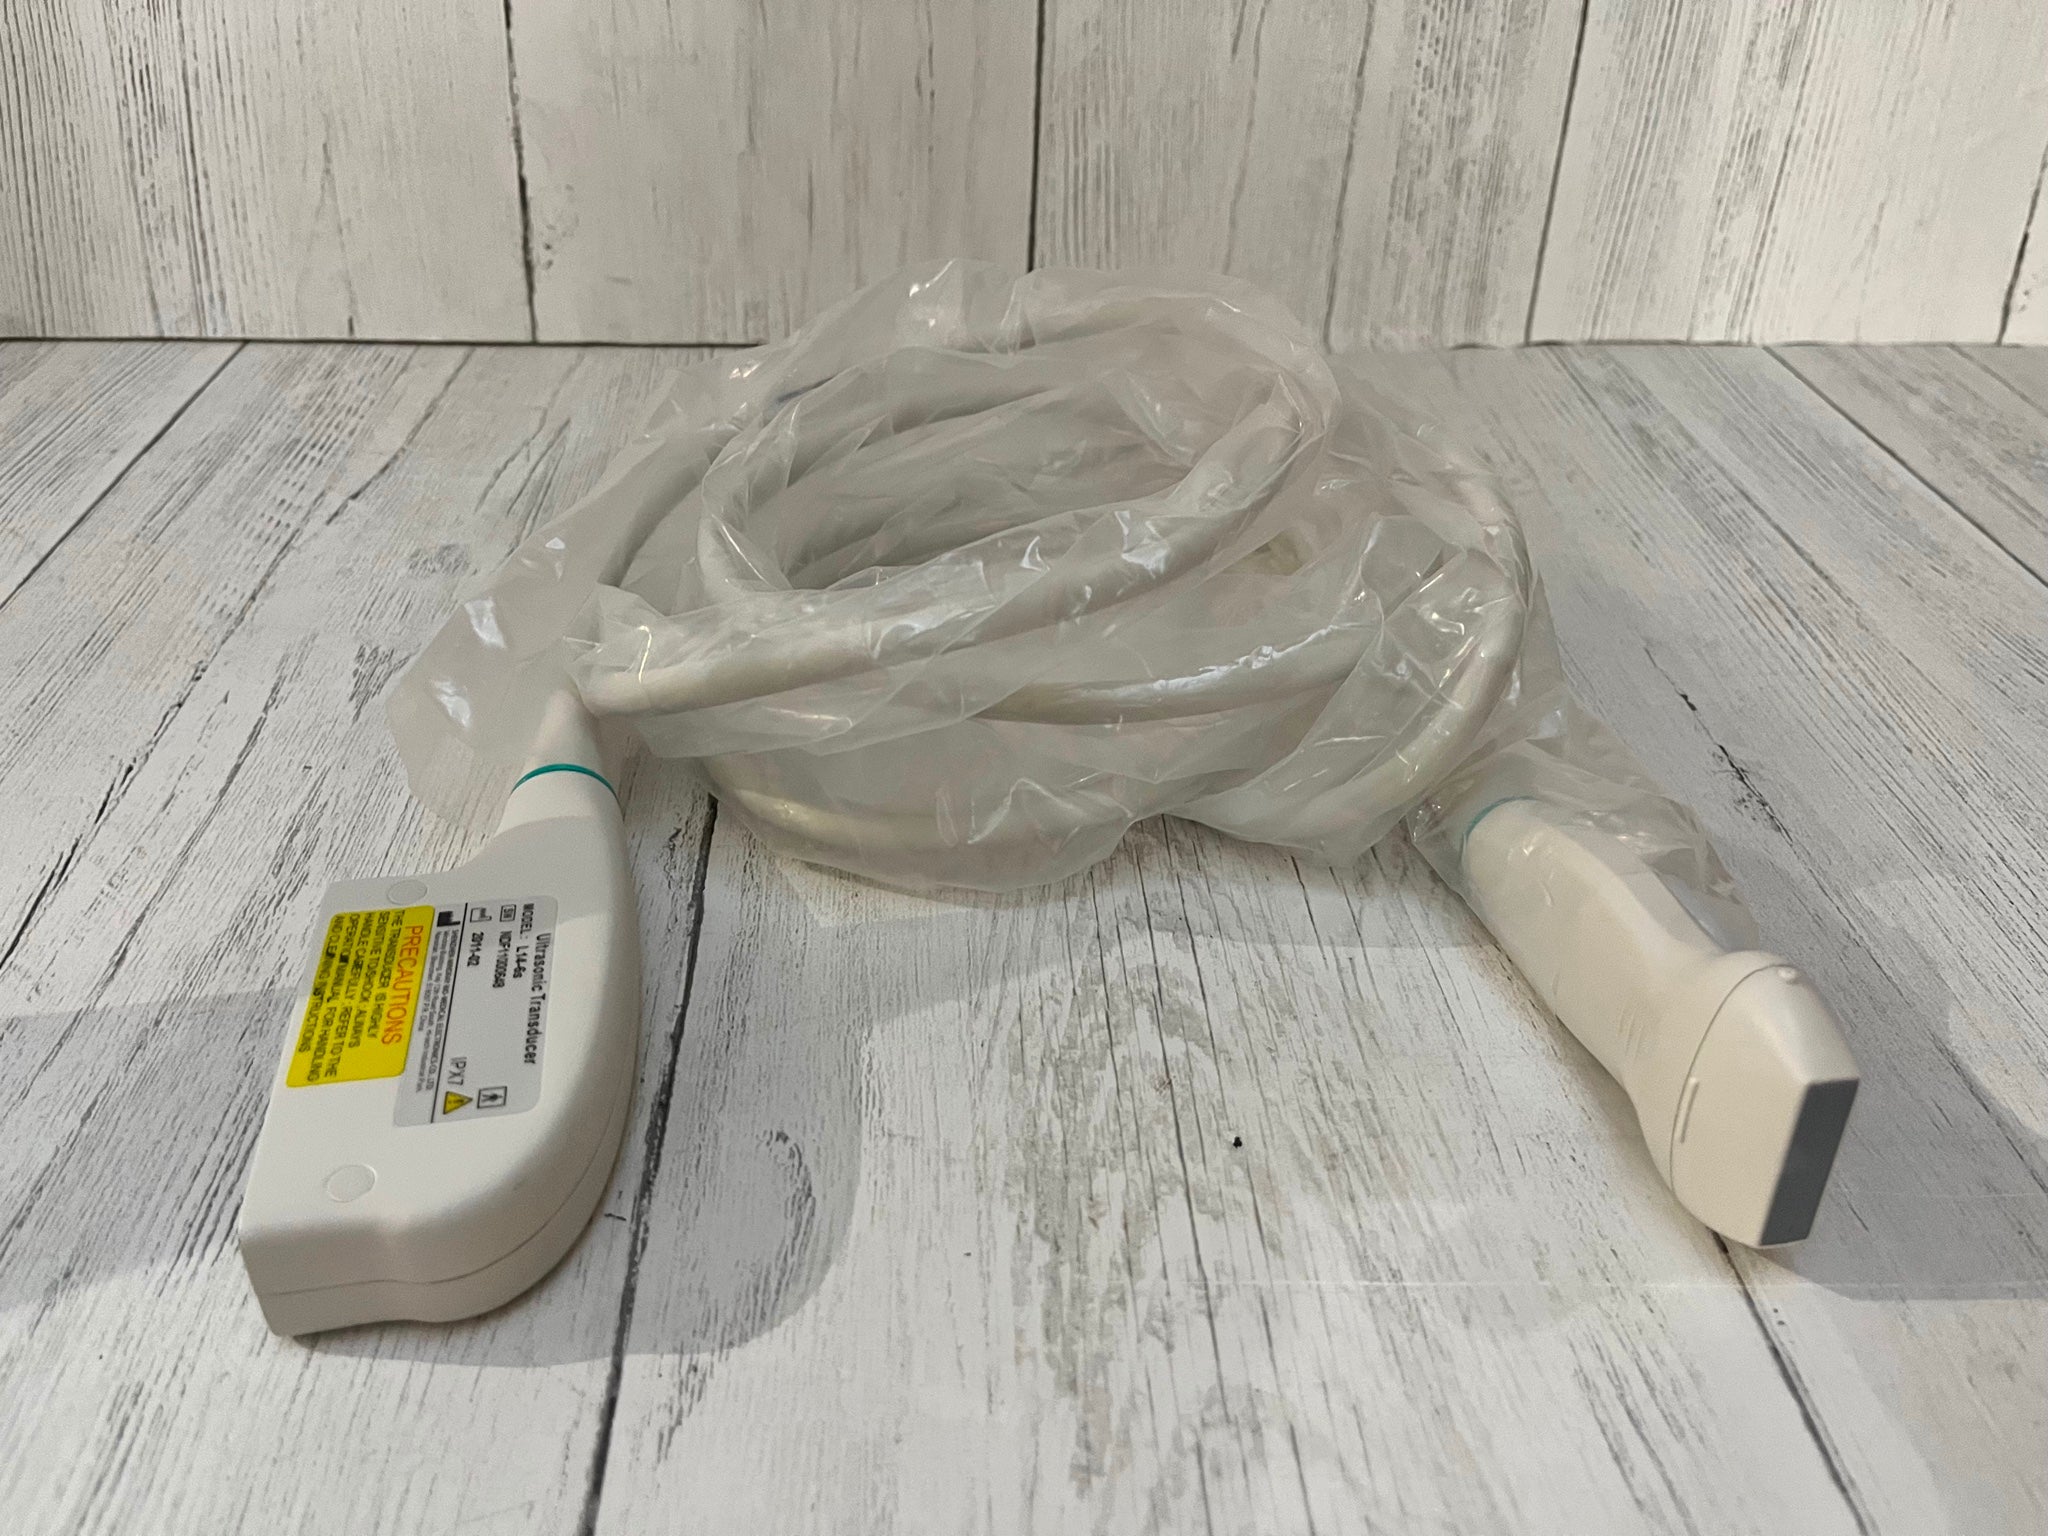

Toshiba Probes

Toshiba Probes

DIAGNOSTIC ULTRASOUND MACHINES FOR SALE